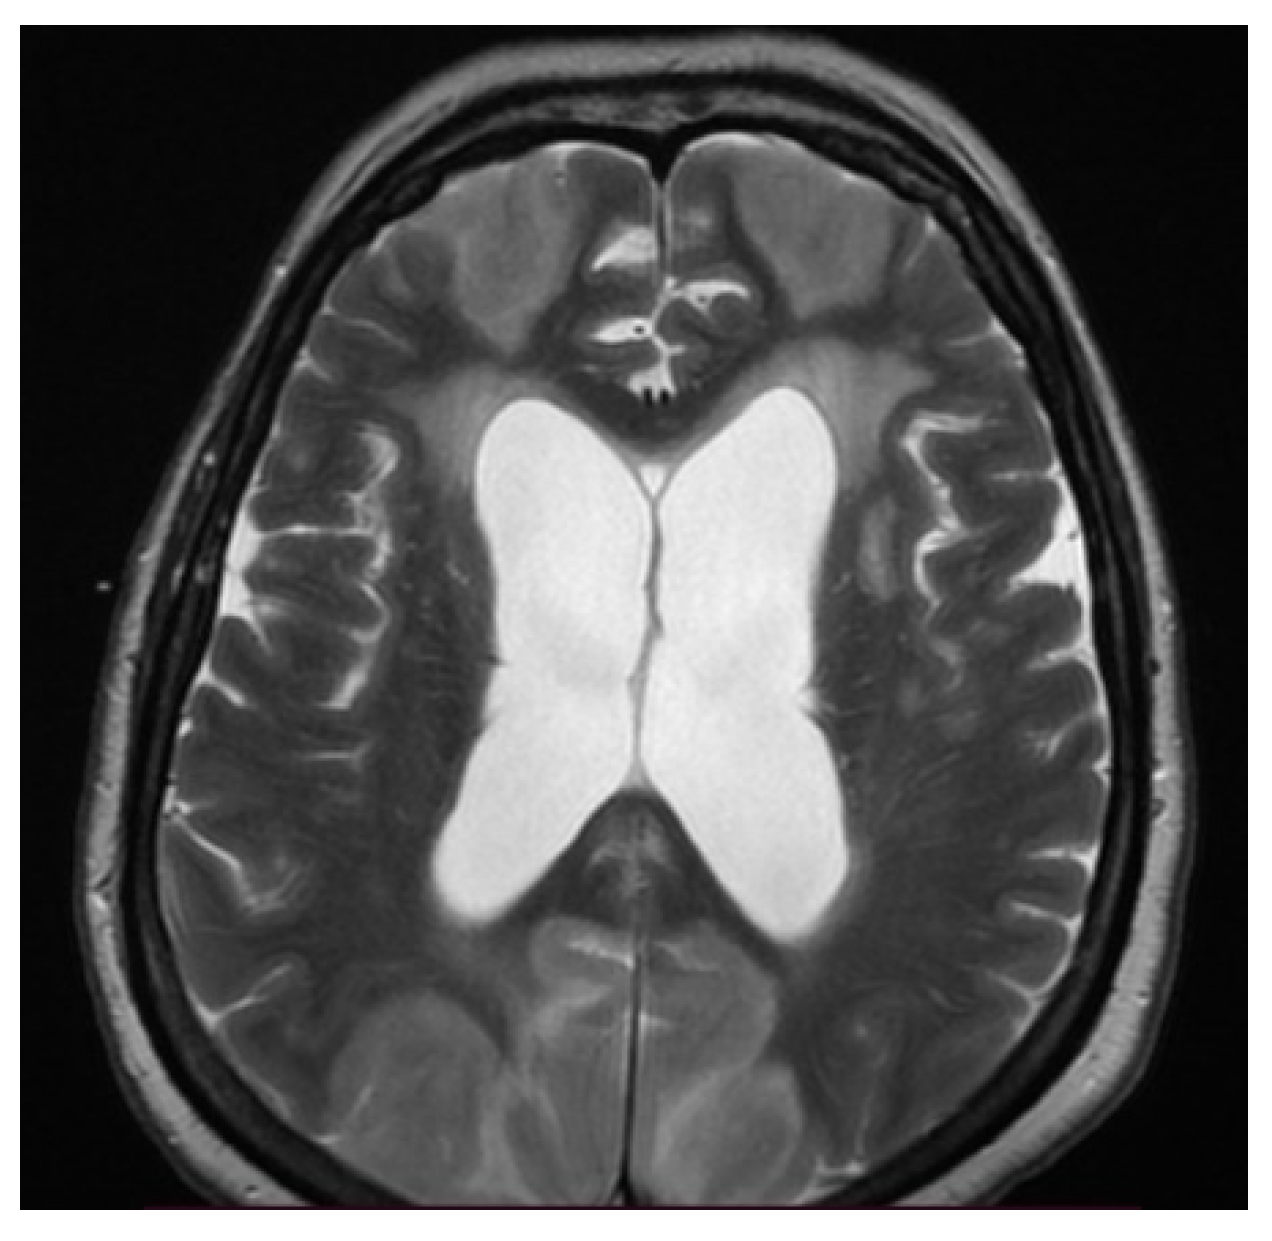

3.3. Neuroimaging